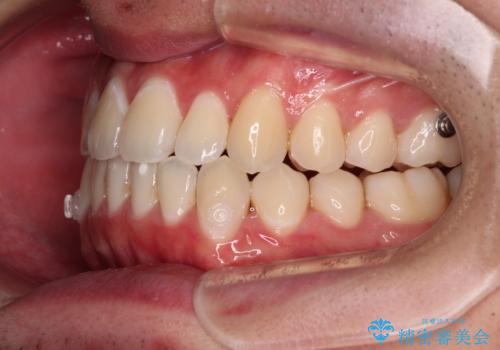

受け口傾向の咬み合わせ インビザラインできれいな口元に

- 前歯のデコボコを治したいとのことで来院された患者様です。

受け口傾向の骨格であり、前歯はクロスバイトまたは切端咬合となっており、叢生は警備であったため、下顎を中心に歯列全体の後方移動を行い、IPR(歯と歯の間を削る)によってデコボコが解消するように設計し、インビザラインにより治療を行うこととしました。

受け口傾向のインビザライン矯正は比較的治療を行いやすいため、きれいに仕上げることができました。舌の突出癖が顕著であったため、改善のためのトレーニングをしっかりと行っていただきました。